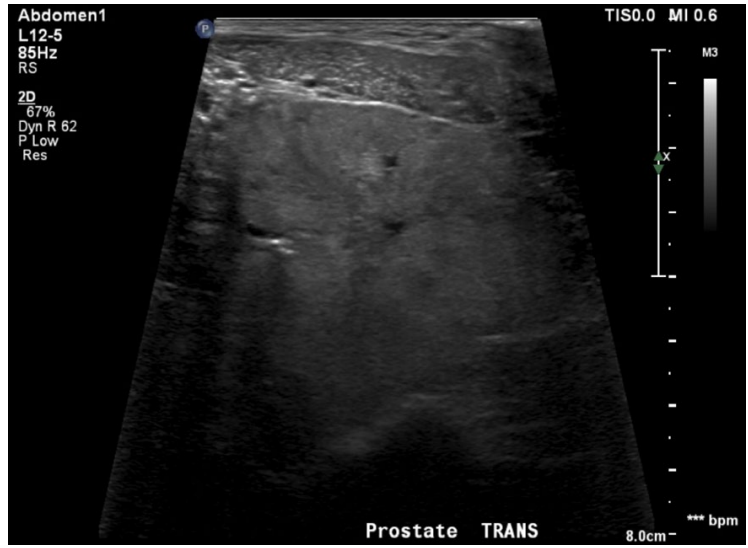

What is shown in this image?

A

benign prostatic hyperplasia

-presence of cysts